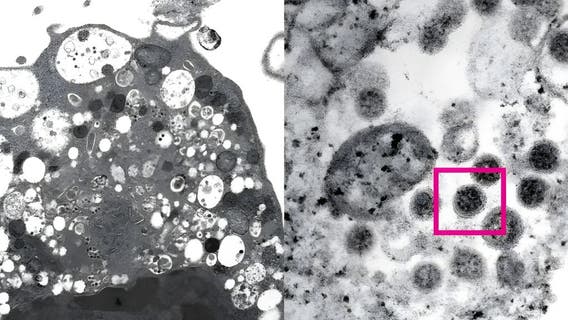

Long COVID: Could mono virus or fat cells be playing a role?

Scientists are still trying to figure out why some people get long COVID and why a small portion have lasting symptoms. Here's some of the latest evidence.